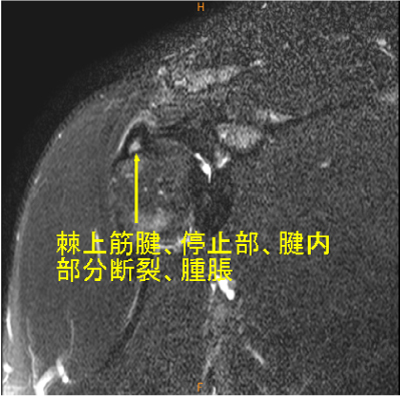

MRI所見

腱内の所見は脂肪抑制T2WIでないと描出するのが難しい。

AC jointの変化は慢性の変化で、棘上筋腱の所見がウエイトトレーニング時の外傷による変化であると想像される。

棘上筋腱停止部腱内の剥離, 腫脹著明, AC-jointのOA